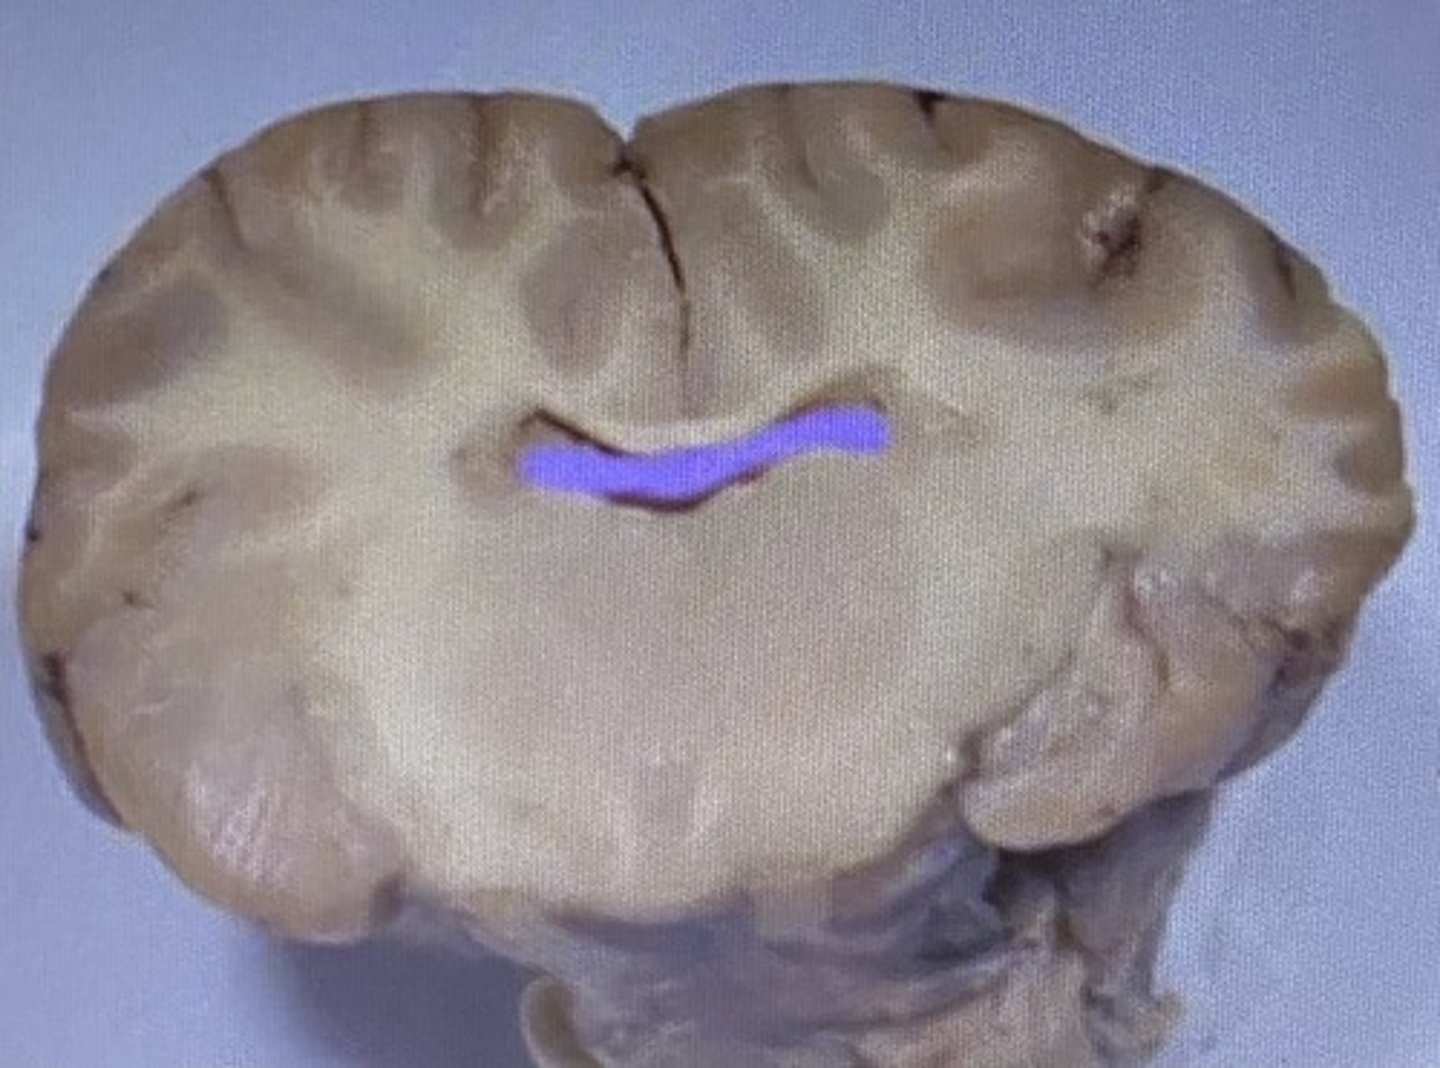

Sheep Corpus Callosum

sheep corpus callosum

Corpus Callosum